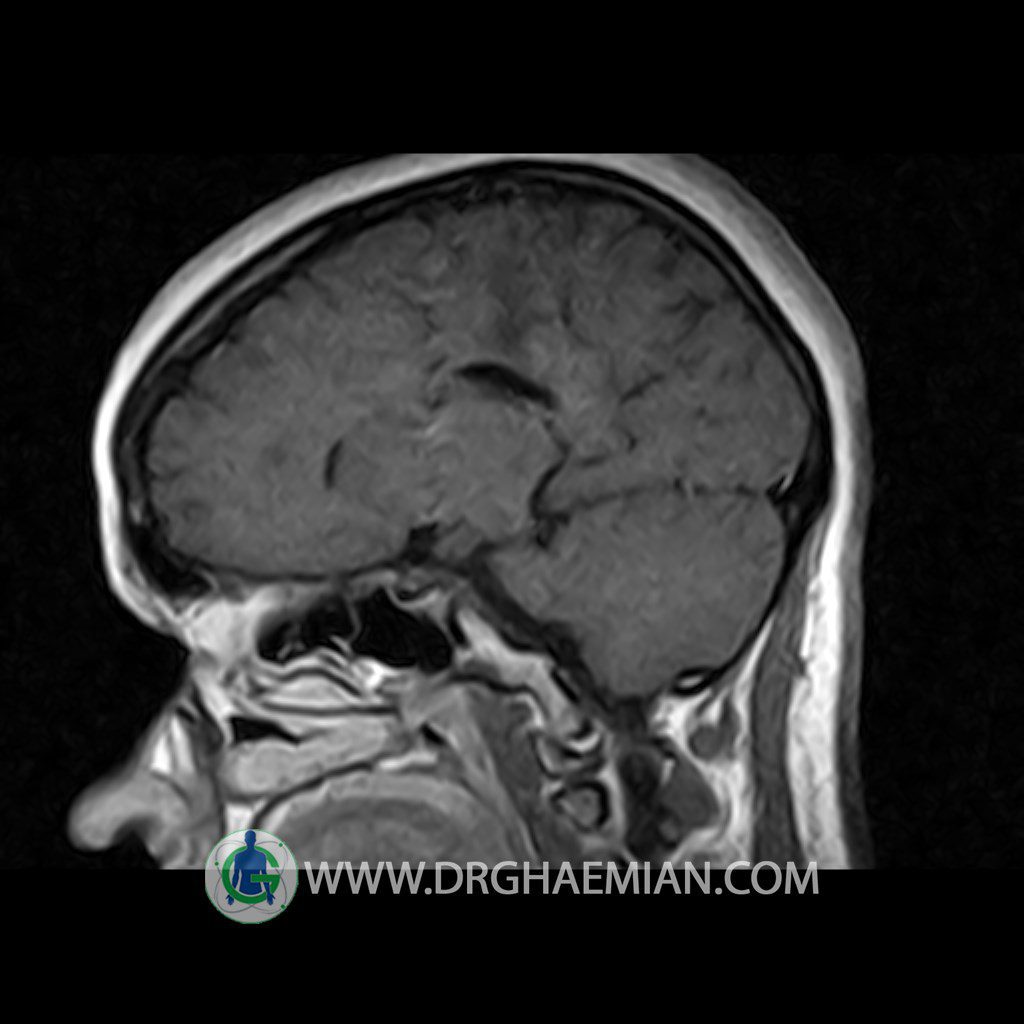

ام آر آی هیپوفیز یک روش تصویر برداری است که از غده هیپوفیز (غده ایی کوچک در مغز که هرومون ها و دیگر غدد بدن را کنترل می کند) و ناحیه های پیرامونش در مغز تصاویری ایجاد می کند. در این کیس سلای نسبتا خالی در ناحیه هیپوفیز بیمار مشاهده می شود.

HYPOPHYSIS MRI

(with and without contrast)

Technique: Axial , coronal T1 , Axial , coronal , sagittal T2 , Axial, coronal T1 post Gd & 64 dynamic thin coronal slices.

REPORT :

The pituitary tissue shows normal , position, shape , size and homogeneous signal intensity both before and after contrast administration .

Anterior and posterior pituitary gland were normal .

It contains no circumscribed hypointense or hyperintense areas .

The infundibulum is centered and of normal size .

The optic chiasm and suprasellar spaces appear normal .

The cavernous sinus and imaged portions of the internal carotid artery and carotid siphon are unremarkable .

Evaluable portions of the neurocranium show no abnormalities .

The sphenoid sinus is clear and pneumatized .

Imaging of the hypothalamus after contrast medium administration was normal.

– Extension of suprasella cistern to sella with thin pituitary gland in floor of sella ( partial empty sella )

is seen